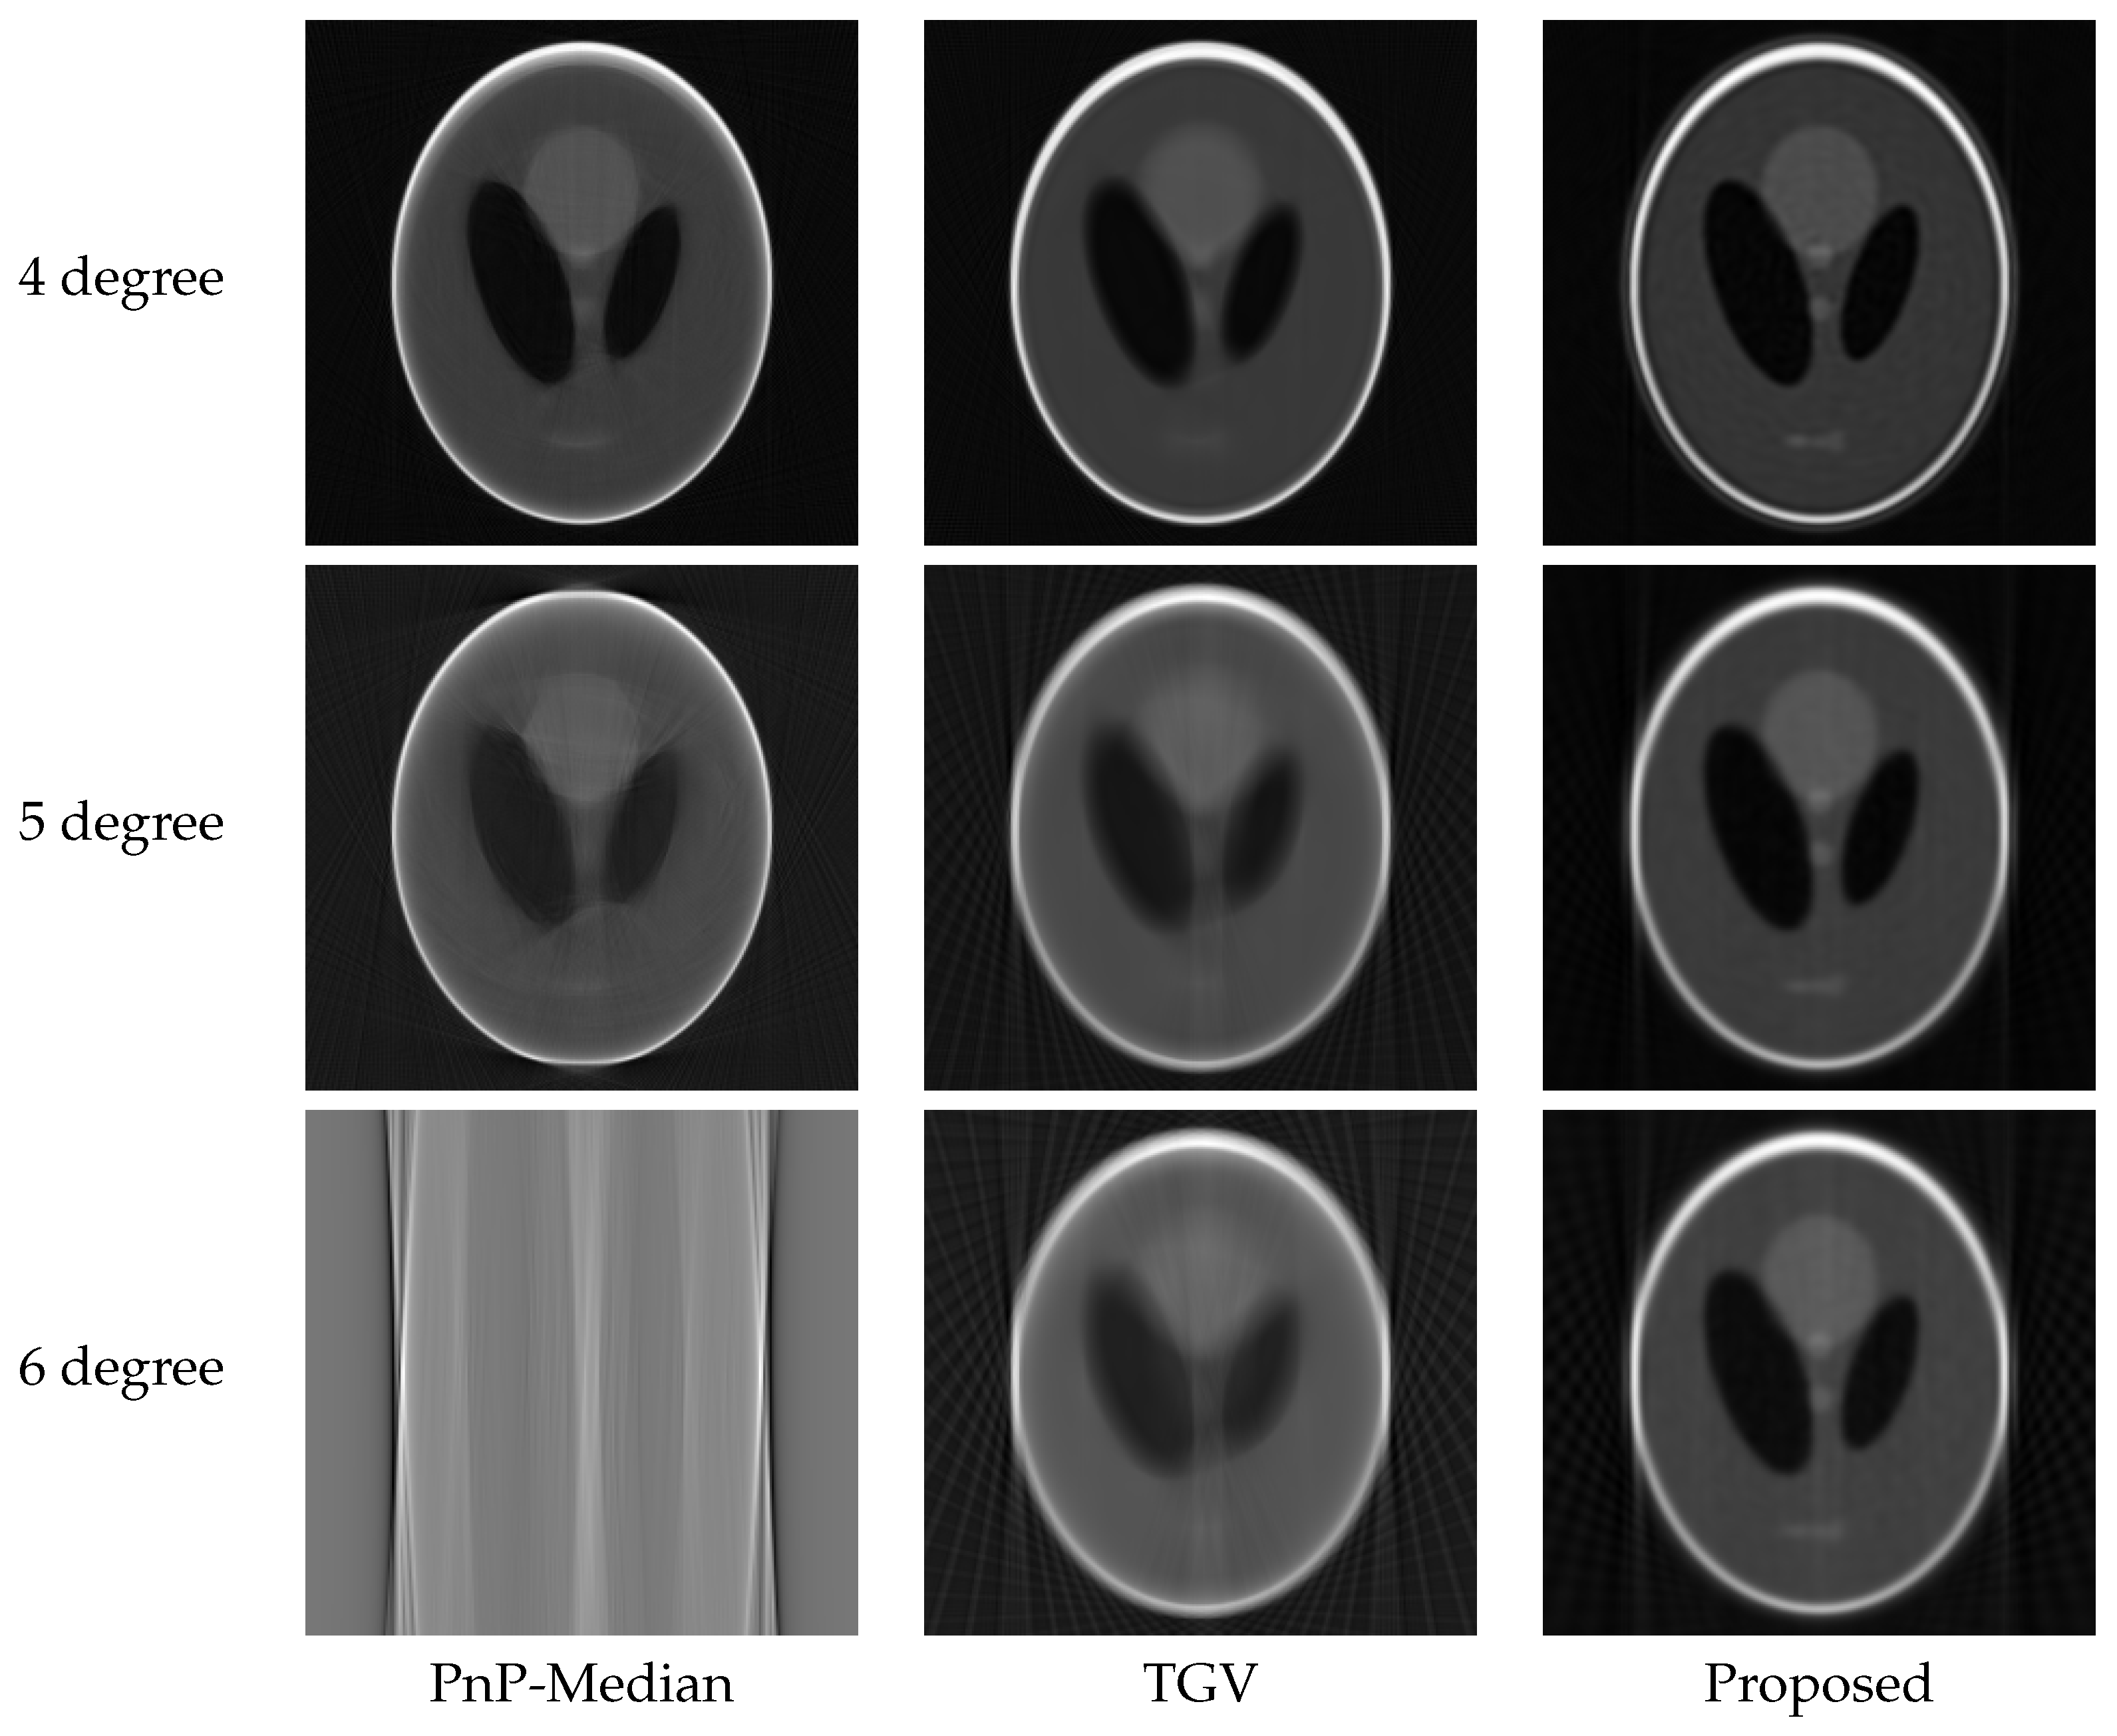

4.3. Experimental Results

| Sinogram | Upsampled Angles | Metric | PnP-Median | TGV | Proposed |

|---|---|---|---|---|---|

| Sinogram 1 | 44 | PSNR | 32.588 | 39.615 | 33.591 |

| SSIM | 0.972 | 0.935 | 0.907 | ||

| Sinogram 2 | 44 | PSNR | 21.159 | 27.249 | 34.933 |

| SSIM | 0.913 | 0.899 | 0.917 | ||

| Sinogram 3 | 44 | PSNR | 36.573 | 38.818 | 42.215 |

| SSIM | 0.974 | 0.919 | 0.930 | ||

| Sinogram 1 | 88 | PSNR | 30.654 | 36.982 | 29.759 |

| SSIM | 0.944 | 0.927 | 0.909 | ||

| Sinogram 2 | 88 | PSNR | 19.833 | 27.006 | 30.424 |

| SSIM | 0.831 | 0.881 | 0.9123 | ||

| Sinogram 3 | 88 | PSNR | 31.8 | 36.275 | 40.914 |

| SSIM | 0.934 | 0.911 | 0.929 | ||

| Sinogram 1 | 132 | PSNR | 11.888 | 32.768 | 24.220 |

| SSIM | 0.784 | 0.911 | 0.901 | ||

| Sinogram 2 | 132 | PSNR | 12.249 | 25.336 | 26.586 |

| SSIM | 0.621 | 0.843 | 0.894 | ||

| Sinogram 3 | 132 | PSNR | 13.330 | 32.742 | 38.190 |

| SSIM | 0.708 | 0.891 | 0.923 |